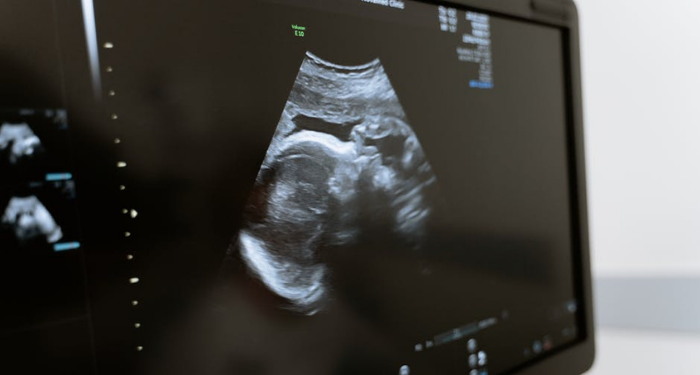

Pemeriksaan oleh dokter termasuk menggunakan USG. Oleh sebab itu, guna mendukung hal ini, salah satu upaya yang dilakukan adalah melalui pengadaan USG Portable di Puskesmas.

Alat USG yang disediakan di Puskesmas akan menjamin proses persalinan yang lebih baik, proses pertumbuhan janin yang lebih baik.

USG portable bisa menjangkau wilayah remote area, daerah perifer di ujung-ujung perbatasan Indonesia. Dengan penggunaan alat USG ini diharapkan para ibu hamil sudah bisa dilakukan deteksi awal apabila ada risiko pada proses persalinannya nanti dan apabila ada gangguan pertumbuhan pada janin pada saat kehamilan.

Dengan USG, rujukan ke rumah sakit bisa dilakukan lebih awal. Sebagai contoh adalah placenta letak rendah atau solusio placenta, ini akan membawa implikasi persalinan dengan perdarahan yang lebih besar dan ini hanya bisa dideteksi dengan alat USG pada saat kehamilan.

Begitu juga dengan ukuran bayi yang besar yang melebihi ukuran, apakah persalinan akan melalui pervaginam atau seksio sesarea bisa dideteksi dengan USG, dan ibu hamil bisa merencanakan sebelum waktu persalinan tiba.